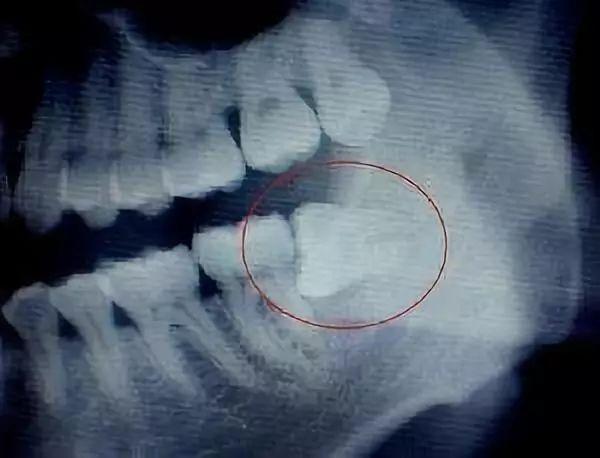

智齒經(jīng)常斜著長,硬的牙冠經(jīng)常頂在鄰牙軟的牙頸部,由于物理擠壓作用,阻生處無法清潔,第二磨牙早于智齒爛牙。

5、垂直中位

由于智齒經(jīng)常斜著長,硬的牙冠經(jīng)常頂在鄰牙軟的牙頸部,由于物理擠壓作用,阻生處無法清潔,第二磨牙早于智齒爛牙。

一顆橫生的智齒,鉗子是搞不出來的。醫(yī)生可以拿出鍾鑿把它劈開搞出來,也可以拿出渦輪機把它磨開搞出來,對患者帶去的影響是一樣的嗎?前者會造成患者心理恐慌,加重關(guān)節(jié)負荷,后者會帶來更高的術(shù)后感染、局部反應風險,能輕易地判斷說哪個方法更先進嗎?只有適合的,沒有好的,這個背后體現(xiàn)的是醫(yī)生的經(jīng)驗和人文關(guān)懷。